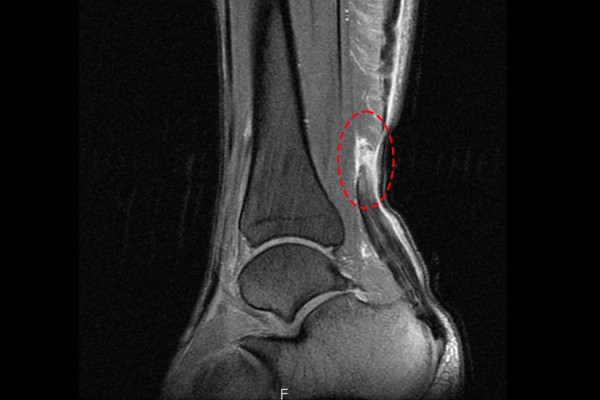

MRI 검사 결과, 파열된 아킬레스건이 확인되어 좌측 아킬레스건 파열(Achilles rupture ankle Lt.)을 진단하였습니다. 이후 환자분께 현재 아킬레스건 상태와 수술의 필요성을 설명드렸고, 수술적 치료인 아킬레스건 다중봉합술[재건술](Ankle Achilles repair)을 시행하였습니다.

수술 후 MRI에서 아키레스건이 일자로 쭉 잘 연결된 것이 확인됩니다.